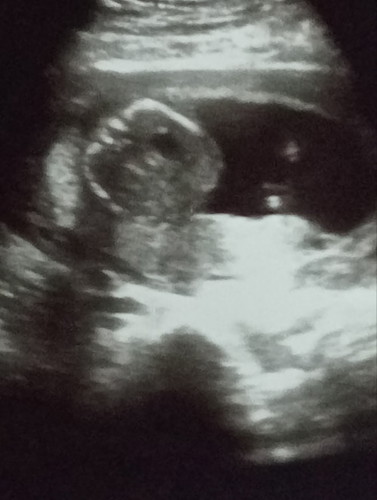

อายุครรภ์ได้17สัปดาห์แล้ว ไม่รู้ว่าเห็นเพศได้หรือยัง

16สัปดาห์นี่ก็รู้ได้แล้วค่ะ แต่ก็อยู่ที่น้องว่าเค้าจะปิดไว้หรือหนีบไว้ให้ไม่เห็นมั้ยเพราะพี่สาวหนูก็น้องไม่ยอมให้ดูเลย เลยรอลุ้นตอนคลอด☺️

บ้านเห็นเห็นเพศน้องตั้งแต่14วีคค่ะ ฝากที่คลินิก แม่ไม่ต้องลุ้นเลยค่ะ ตั้งมาเลย เพศชาย

ของบ้านนี้18+5แล้วยังไม่รู้เพศเลยหมอบอกประมาณ20สัปดาห์ถึงจะดูให้ แม่่ฝากรัฐบาลค่ะ